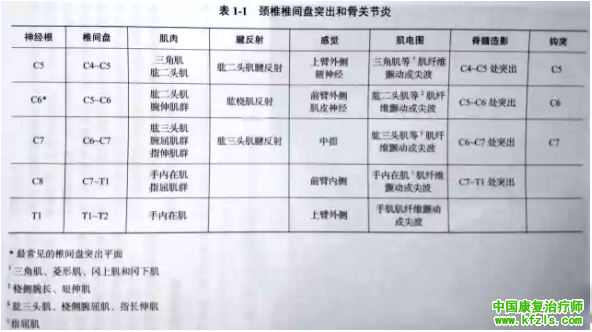

表1-1 归纳了颈椎各平面的神经功能检査方法, 同时也总结了其在颈髓病变尤其是颈椎间盘突出症中的临床应用。

2.肌电图:该技术能准确地检测运动电位。神经损伤2周后即可检测到静息肌肉的不自主放电反应(肌纤维颤动电位和正尖波)。

肌电图还可检测出肌肉的去神经化表现,这可由椎间盘突出、神经根撕裂伤或者脊髓损伤导致,亦可由神经丛或者外周神经损伤引起。在临床检査时,对判断神经节段(肌节)的代表肌肉应进行完整的评估(详见表1-1 )。